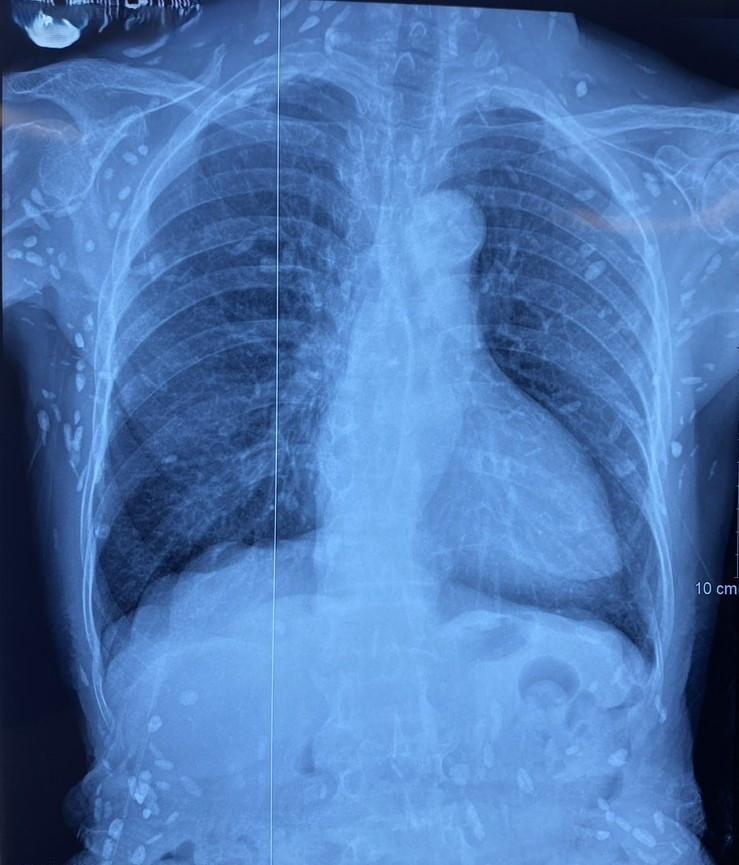

Người bệnh được chuyển lên từ tuyến trước vì rối loạn ý thức đe dọa suy hô hấp, hình ảnh cắt lớp vi tính sọ não và X-quang ngực cho thấy rất nhiều nốt cản quang trong nhu mô não và dưới da vùng ngực-bụng.

san-day-lon.jpg

Nhiều nốt cản quang dưới da thành ngực-bụng và chi trên - Ảnh BVCC

Nang sán dây lợn có thể tự thoái hóa hoặc bị vôi hóa, tạo nên nhiều hình ảnh cản quang phát hiện được trên phim X-quang như trường hợp bệnh nhân trên.